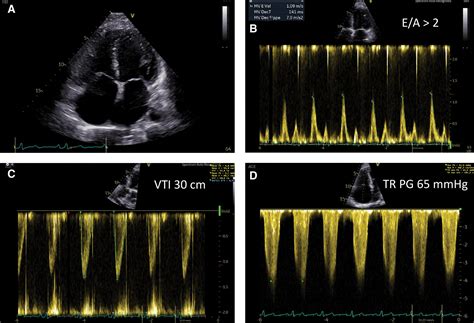

To confirm the diagnosis, medical teams typically rely on a combination of imaging and laboratory markers. An echocardiogram is essential, as it will demonstrate a hyperdynamic heart with a high ejection fraction—the exact opposite of what is seen in traditional heart failure. Additional steps include: